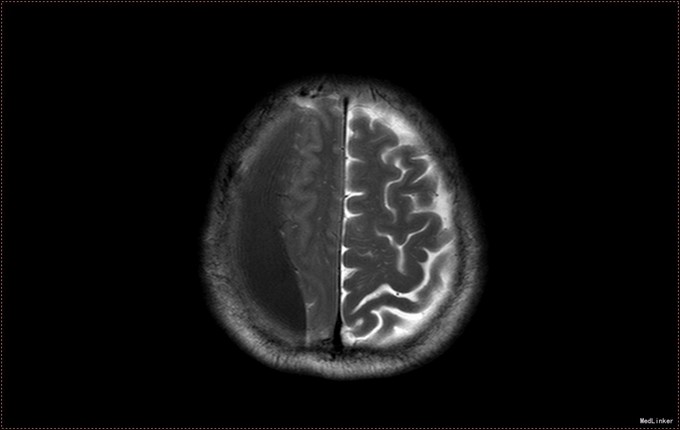

患者,男,53岁。以“左侧肢体疼痛伴无力1周”为主诉入院。患者1周前无明显诱因出现左侧肢体无力,伴酸痛,头部闷胀感,症状持续不缓解,于我院就诊,行头部CT及MR提示右侧顶枕叶硬膜下血肿。右侧额颞叶蛛网膜囊肿。患者为求进一步治疗,急诊以“硬膜下血肿”为诊断,收入病房。患者病来精神状态差,饮食睡眠可,二便可,体重无明显变化。否认近期头部外伤史。

入院查体:T:36.5℃ ,P:68次/分 ,BP:130/80mmHg , R:16次/分。步入病房,自主体位。神清语明,问答准确,查体合作,精神状态良好,定向力完整。粗测视野正常,双侧瞳孔等大正圆,D≈3.0mm,双侧眼球活动自如,对光反射灵敏。四肢活动自如,左侧肢体肌力V-级,右侧肢体肌力Ⅴ级,肌张力正常。深浅感觉检查未见异常。头CT及MR提示右侧颞极蛛网膜囊肿,右侧亚急性硬膜下血肿

患者诊断明确,完善术前检查行局麻右侧钻孔冲洗引流术,予常规治疗。术后3天拔管,复查头CT硬膜下血肿消失,但脑组织膨胀不良。患者左侧肢体肌力恢复正常,无头晕头沉症状,顺利出院。